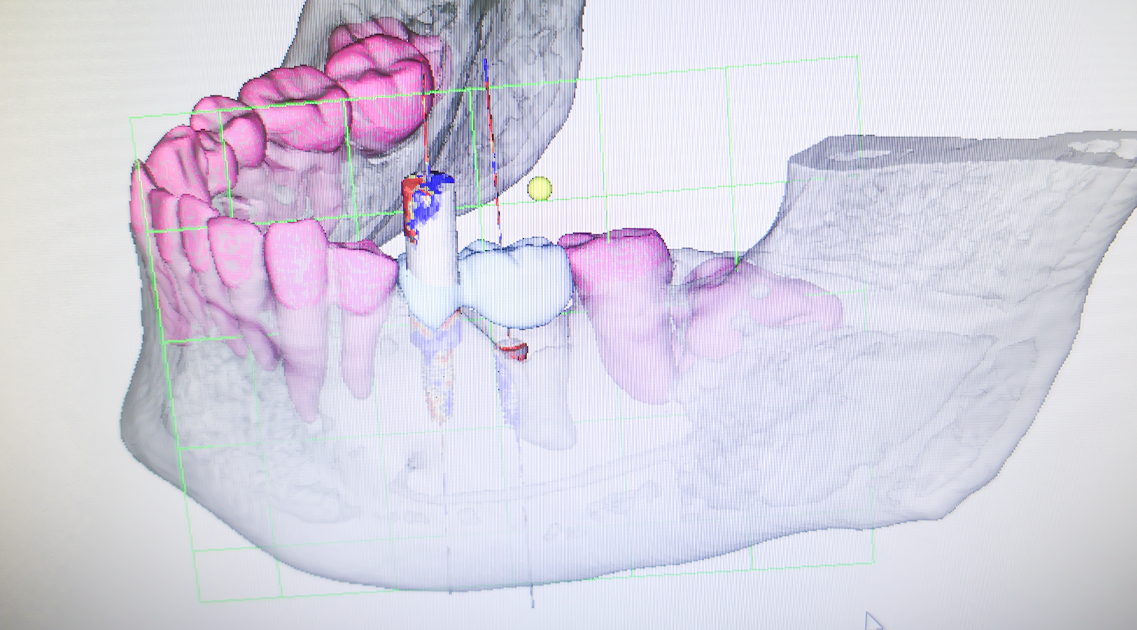

BioNaシミュレーション画像

BioNaシミュレーション画像 歯牙支持型フラップレス

歯牙支持型フラップレス